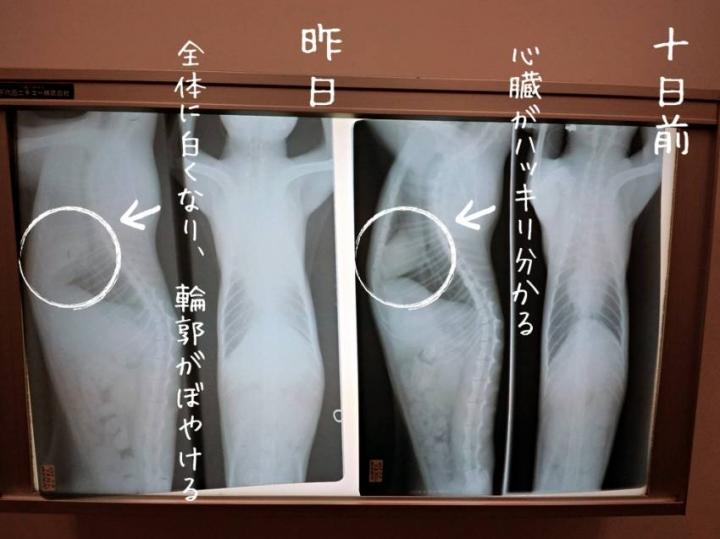

キムンの呼吸がやや荒くなり、

病院に駆け込んでレントゲンを撮影していただきました。

10日ほど前に撮影したものと、

昨日のものを見比べると、

胸水が再び溜まってきていたことが確認できました。

↑先日のものでは心臓の境界線が見えにくくなっていました